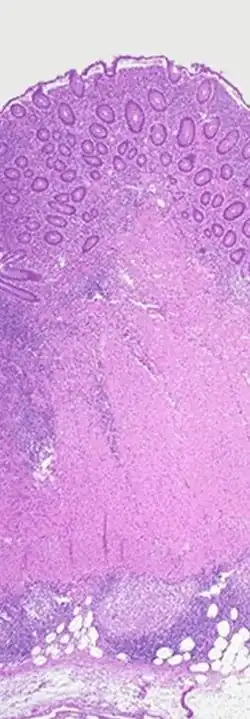

Feingewebsschnitt, Morbus Crohn

Makroskopisch sind folgende Veränderungen charakteristisch:

Histologisch (feingeweblich) erkennt man vor allem eine Häufung von Lymphozyten, (eosinophilen) Granulozyten und Histiozyten in der Biopsie des entzündeten Darmgewebes. Angrenzende Lymphknoten sind meist vergrößert. Häufig bilden sich Granulome (inkonstant und keineswegs pathognomonisch), die sich in zwei Typen unterscheiden lassen: Epitheloidzellgranulome und Mikrogranulome (kleiner und ohne zentrale Nekrose).